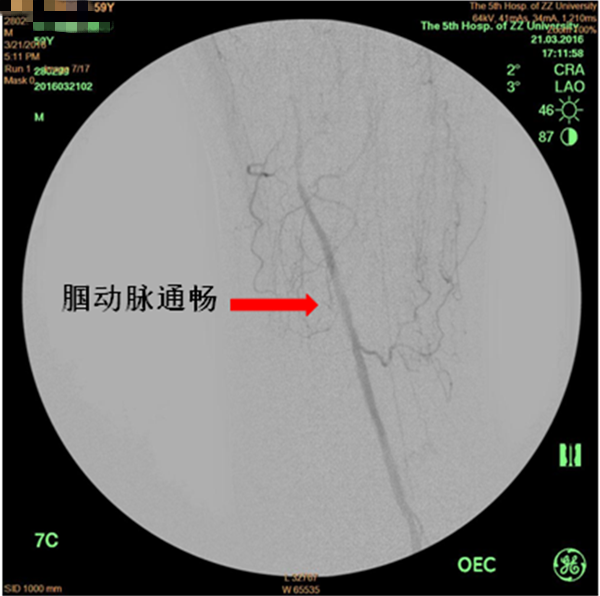

患者周先生,59岁,1年前无明显原因出现双侧小腿及足部发凉,活动后左足疼痛,3月前疼痛加重,出现左足第4及第5足趾发紫,并逐渐进展为足趾发黑、坏死,多处求医用药治疗,效果差,2周前左足疼痛进一步加重,并累及左足第3足趾发黑坏死,无法行走,严重影响了病人的生活质量(见图1)。慕名前来我院血管外科就诊。我院血管外科专家王兵教授为患者制定了详细的诊疗方案,下肢动脉CTA提示患者左侧股浅动脉多发粥样硬化斑块形成,管腔长段闭塞(见图2),明确诊断为“复杂下肢动脉硬化闭塞症”,积极术前准备后,王兵教授带领血管外科崔文军副主任、安乾主治医师、李攀峰医师给患者进行血管腔内介入治疗。术中DSA造影提示:股浅动脉长段闭塞,腘动脉通畅(见图3、图4)。单弯导管配合超滑导丝及微导丝,反复多次尝试顺行开通股浅动脉闭塞段均宣告失败,王兵教授决定采用逆穿技术,在DSA下穿刺腘动脉,成功后逆行置入单弯导管及超滑导丝,顺利开通股浅动脉闭塞段,逆行超滑导丝选入顺行单弯导管内,完成对接(见图5、图6),逆行导丝引出体外,引入球囊扩张股浅动脉闭塞段,股浅动脉闭塞段置入两枚金属裸支架后造影显示左下肢动脉全程通畅(图7、图8)。术后患者胫后动脉搏动恢复,静息性疼痛消失。 复查下肢动脉CTA:左下肢动脉血流通畅(图9)。

图4